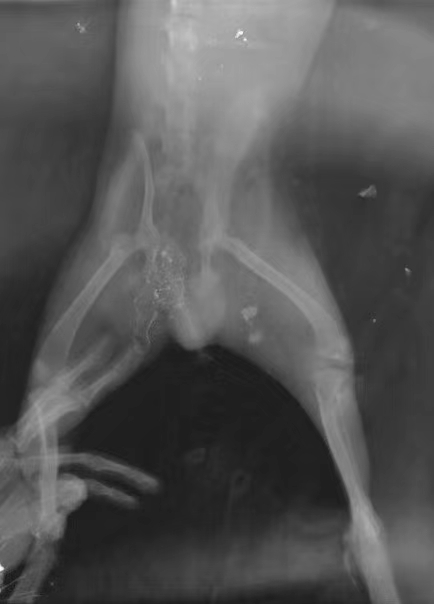

車禍/咬傷各一例: 泰迪,被車碾壓挫傷,導(dǎo)致皮膚開裂,骨折,實(shí)施緊急手術(shù)處理;約克夏,summer,溜狗時(shí)被大型犬咬傷于臀部,實(shí)施傷口清洗,壓迫縫合。Ps:  過年了,注意安全,注意安全,帶好牽引繩,保護(hù)好自家寶貝。